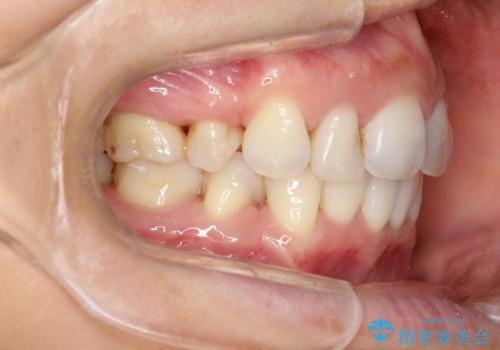

- 上下の歯のがたつきを主訴に来院されました。

上下の前歯の叢生とかみ合わせが深い過蓋咬合という状態でした。

上下左右の歯を1本ずつ抜歯して、ワイヤーにて矯正を行いました。

かみ合わせの深さを改善するのに時間がかかり、予定よりも治療期間が長期化しましたが、整った歯並びへ改善することができました。